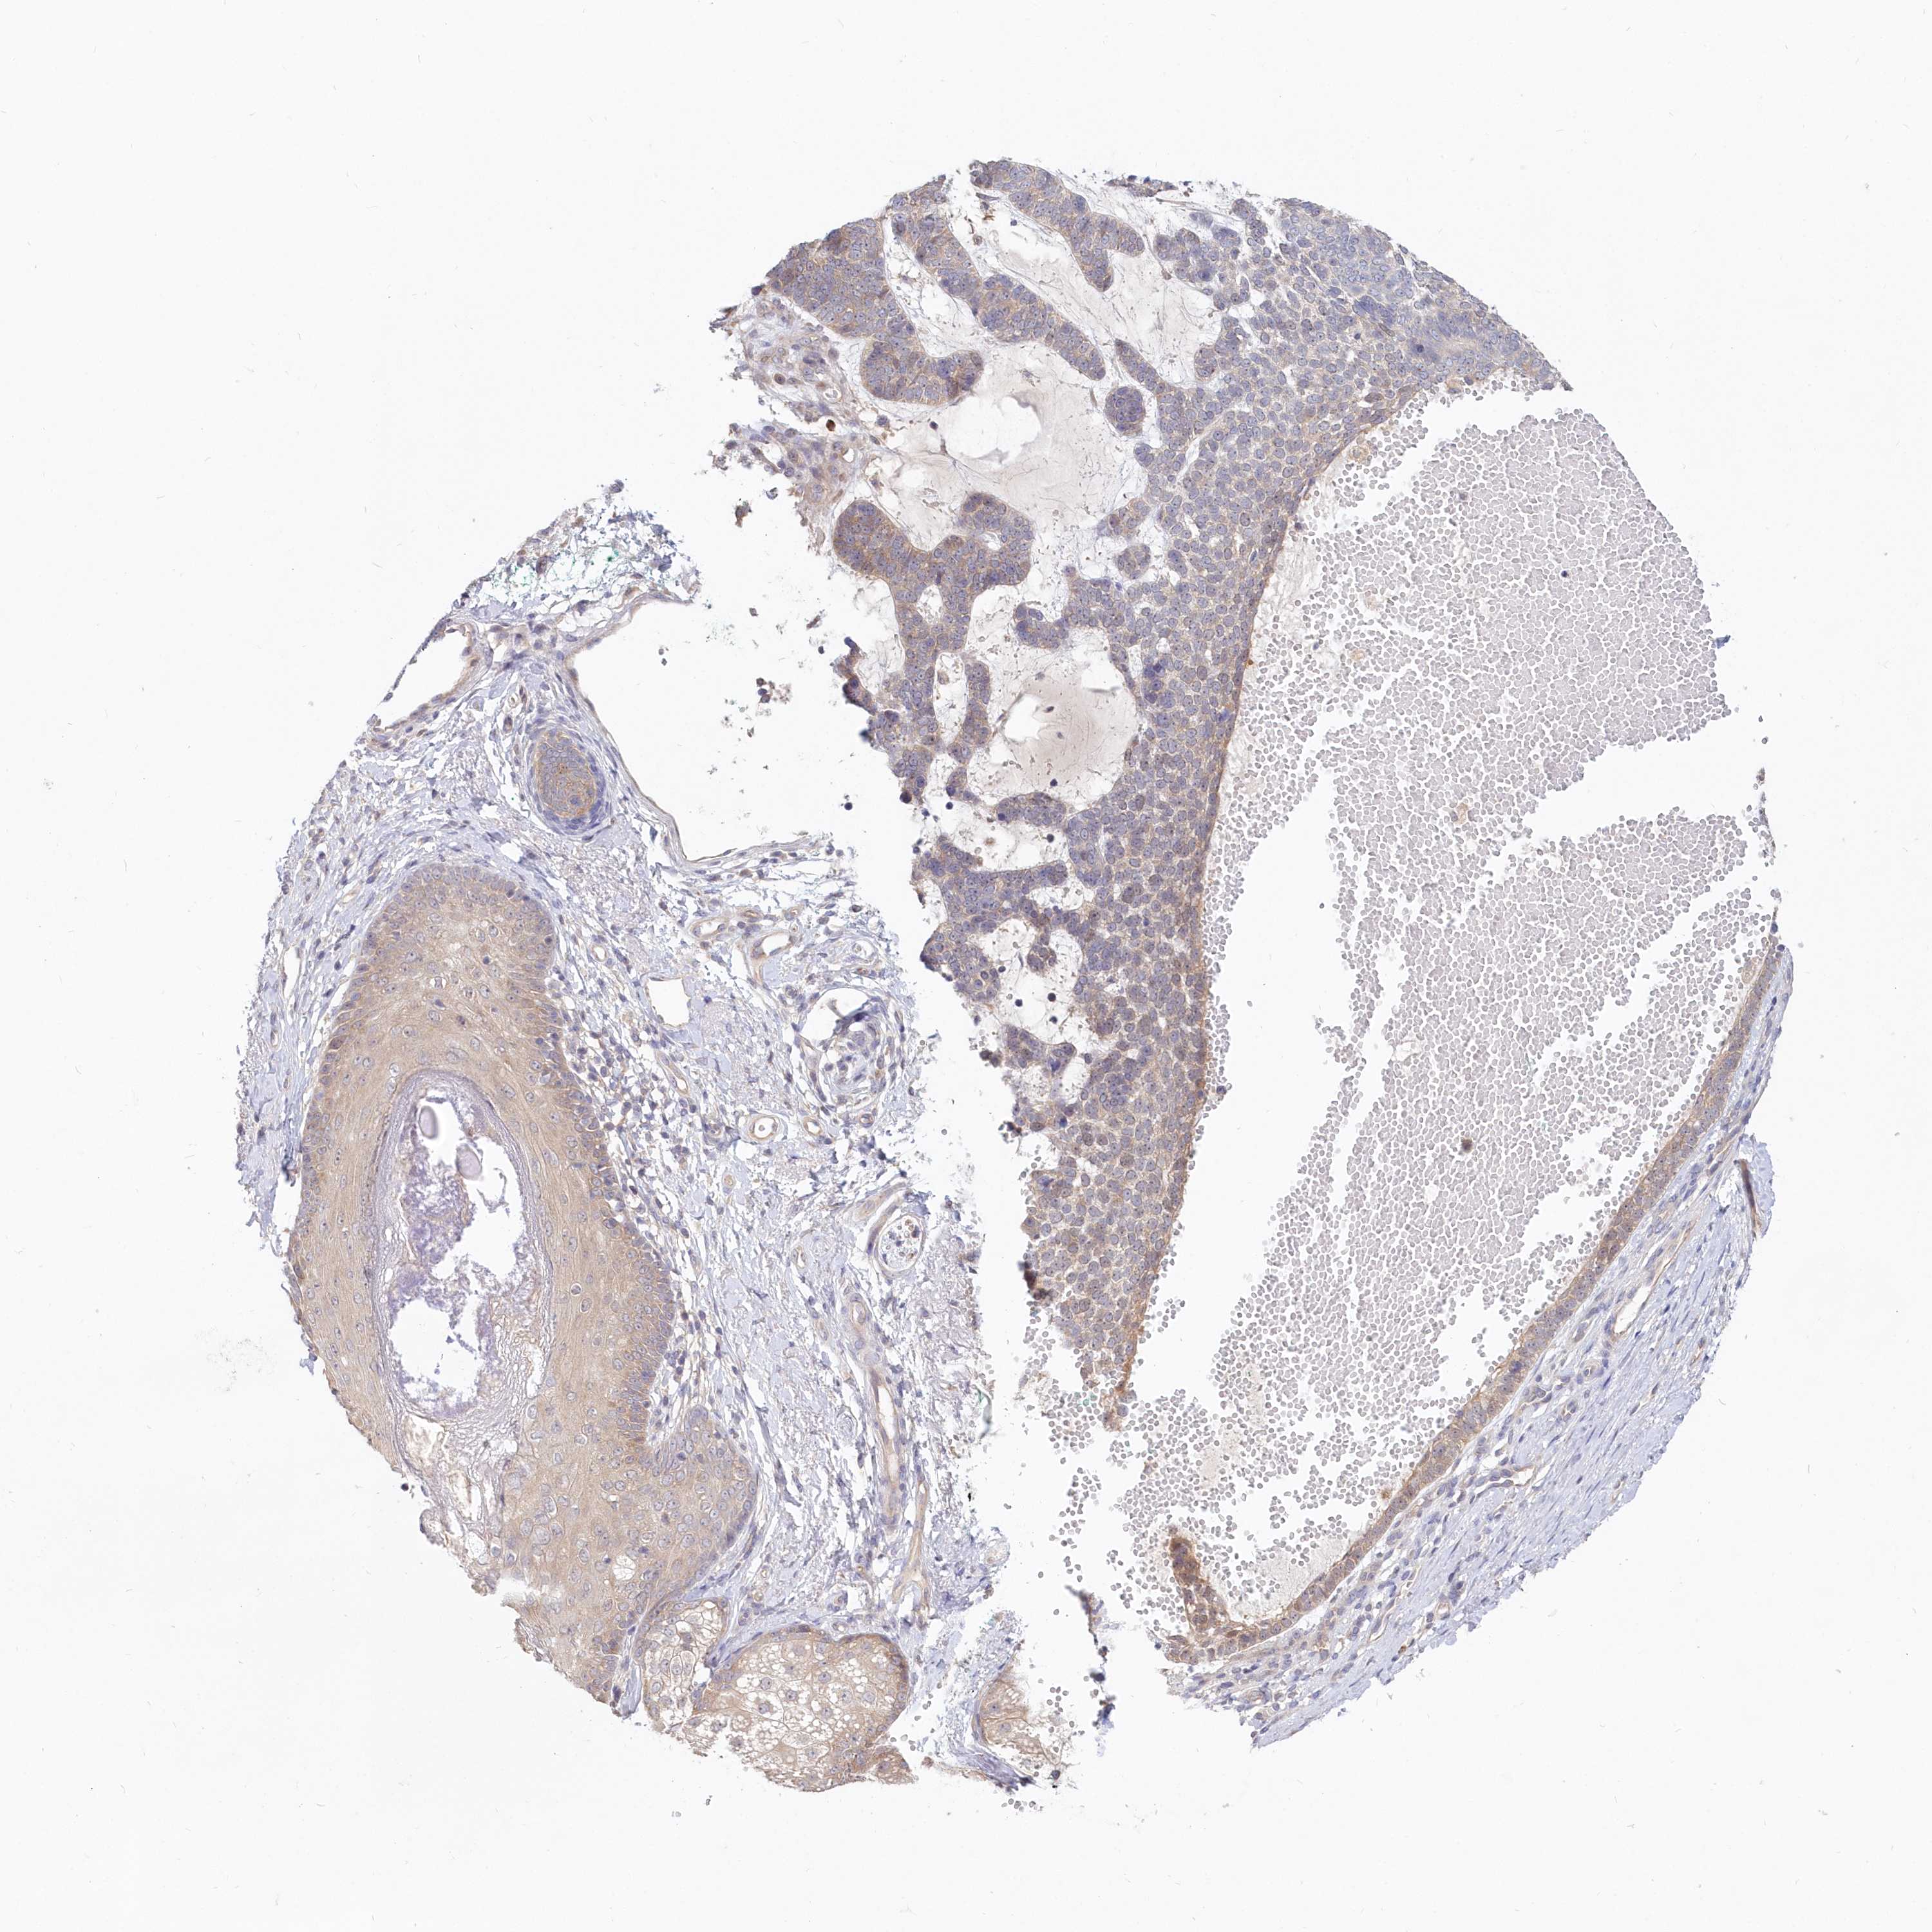

Basal cell and squamous cell cancer

SKIN CANCER - Protein expressioni

A mouse-over function shows sample information and annotation data. Click on an image to view it in a full screen mode. Samples can be filtered based on level of antibody staining by selecting one or several of the following categories: high, medium, low and not detected. The assay and annotation is described here.

Antibody stainingi

Antibody staining in the annotated cell types in the current human tissue is reported as not detected, low, medium, or high, based on conventional immunohistochemistry profiling in selected tissues. This score is based on the combination of the staining intensity and fraction of stained cells.

Each image is clickable and will lead to virtual microscopy that enables deeper exploration of all samples and also displays staining intensity scores, fraction scores and subcellular localization as well as patient and tissue information for each sample.

Antibody HPA036207

Staining

High

Medium

Low

Not detected

Intensity

Strong

Moderate

Weak

Negative

Quantity

>75%

75%-25%

<25%

None

Location

Nuclear

Cytoplasmic/membranous

Cytoplasmic/membranous,nuclear

Squamous cell carcinoma, NOS